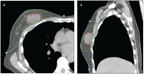

FIGURE 1

Axial (A) and Sagittal (B) Images Showing the Target Areas in Breast Radiation.

Accelerated partial-breast irradiation (APBI) is an approach in which only the area of the breast where the tumor was initially located is targeted with radiation, with treatment typically delivered over 1 to 15 days. While WBI typically encompasses the breast parenchyma, chest wall musculature, ribs, and approximately 60% of the level I and II lymph nodes, APBI focuses radiation on a 1- to 2-cm margin of tissue surrounding the lumpectomy cavity (Figure 1). The rationale for irradiating only part of the breast stems from the observation that the majority of breast cancer recurrences following lumpectomy alone occur adjacent to the lumpectomy cavity, as evidenced by data from three randomized trials comparing treatment with lumpectomy alone with lumpectomy followed by WBI.[1,3,4] Indeed, in these studies, the incidence of treatment failures elsewhere in the breast, far from the initial tumor bed, occurred at the same rate in patients who received WBI as in those who did not, implying that the main local benefit of WBI is in the area of the tumor bed. Irradiating less of the breast would reduce dose to uninvolved breast tissue, the lungs, the ribs, the chest wall musculature, and the heart, all of which might reduce the risk of late complications.[5]